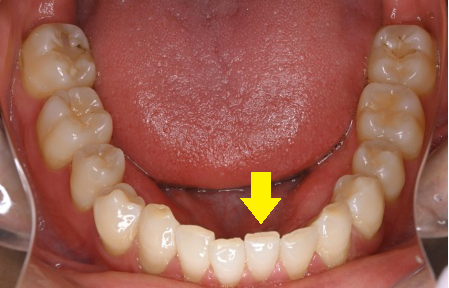

↑むし歯にはなっていませんが、ぶつけて欠けたケース